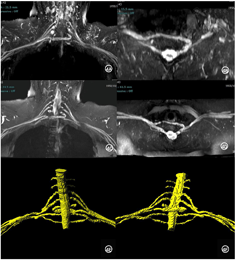

为明确臂丛神经、周围动静脉关系情况进行精准术前规划、减少神经血管损伤,患者进行了基于增强前后三维短时反转恢复各向同性变翻转角激发序列(3D-T2-sampling perfection optimized contrasts by using different flip angle evolution short time inversion recovery,T2-SPACE-STIR)的臂丛神经高分辨MRI检查。

患者拟行健侧颈7神经交叉移位术,行臂丛神经MR目的在于了解臂丛神经分布、有无解剖变异,术前测量颈7神经干可安全切取的长度,判定能否满足交叉移位的长度为影像评估重点。将本病例原始薄层图像输入西门子图像后处理工作站syngo.via,通过MM Research Frontier图像后处理软件进行分割重建,构建臂丛神经个体化三维数字模型,显示双侧臂丛神经形态及走行分布未见异常(图3A、C-D),沿C7神经走行进行多平面重组或曲面重组图像重建,测量C7神经根自椎间孔至前后股合束前的神经长度,本例约6.5cm(如图3B)。

患者行健侧颈神经交叉移位术,术中:暴露健侧C7神经根,向远端分离至前、后股合束水平,近端分离至近椎间孔水平,测量前股6.3 cm、后股6.5 cm。术中显微镜下,行健侧C7神经前后股-患侧C7神经根缝合,吻合牢靠无张力。